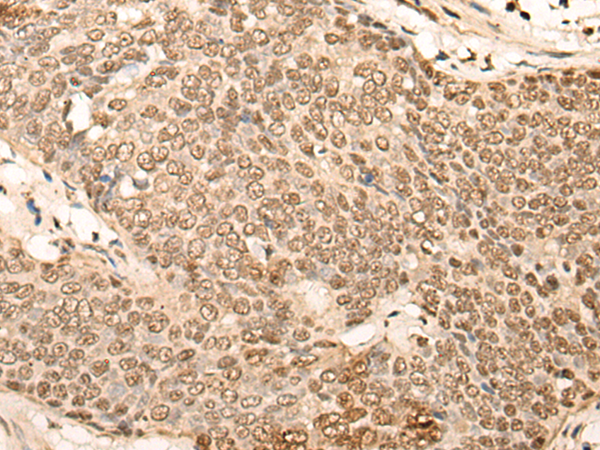

IHC positive control: |

Human esophagus cancer and Human breast cancer |

IHC Recommend dilution: |

50-300 |